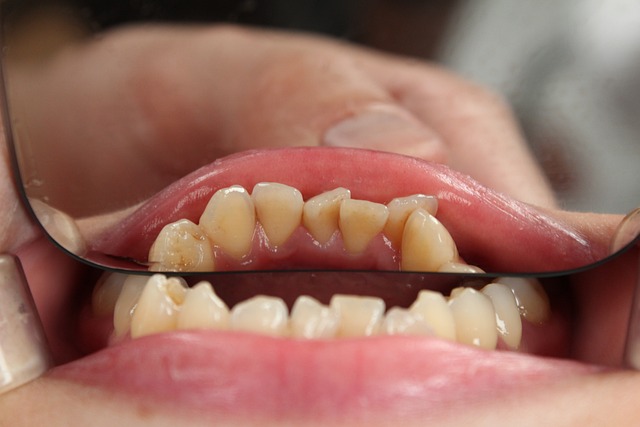

사랑니는 어금니 뒤쪽에 나는 세 번째 어금니로, 보통 10대 후반~20대 초반에 나기 시작합니다. 하지만 사랑니가 정상적으로 나지 않거나, 부분적으로 잇몸에 묻힌 경우에는 여러 문제를 유발할 수 있습니다.

✔ 부분 매복 사랑니: 일부만 잇몸 밖으로 나와 음식물이 끼고 충치 발생 가능

✔ 완전 매복 사랑니: 잇몸 속에 갇혀 염증, 통증, 신경 손상 유발 가능

✔ 옆으로 누운 사랑니: 앞 치아를 밀어 치열이 틀어지고 통증 발생